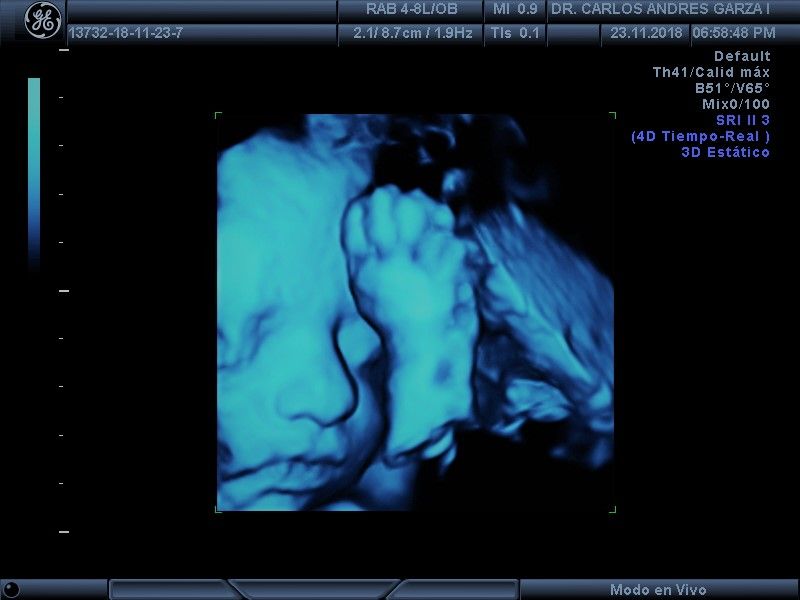

Ultrasonido 4D

!Conoce a tu bebé hoy¡ Se trata de la última tecnología en ecografía o ultrasonido a nivel mundial, que consiste en un procesamiento de reconstrucción digital de imágenes para formar una sola imagen en 4 dimensiones, permitiendo así poder visualizar cualquier estructura tal cual la estuviésemos viendo directamente el rostro de tu bebé, antes de nacer. Con esta nueva generación de tecnología del ultrasonido puedes observar datos mas detallados de su bebé, sus movimientos, gestos, risas, bostezo, etc... tal como si lo tuviera en sus brazos. En el pasado los papas no conocían la cara de su bebe hasta que naciera.